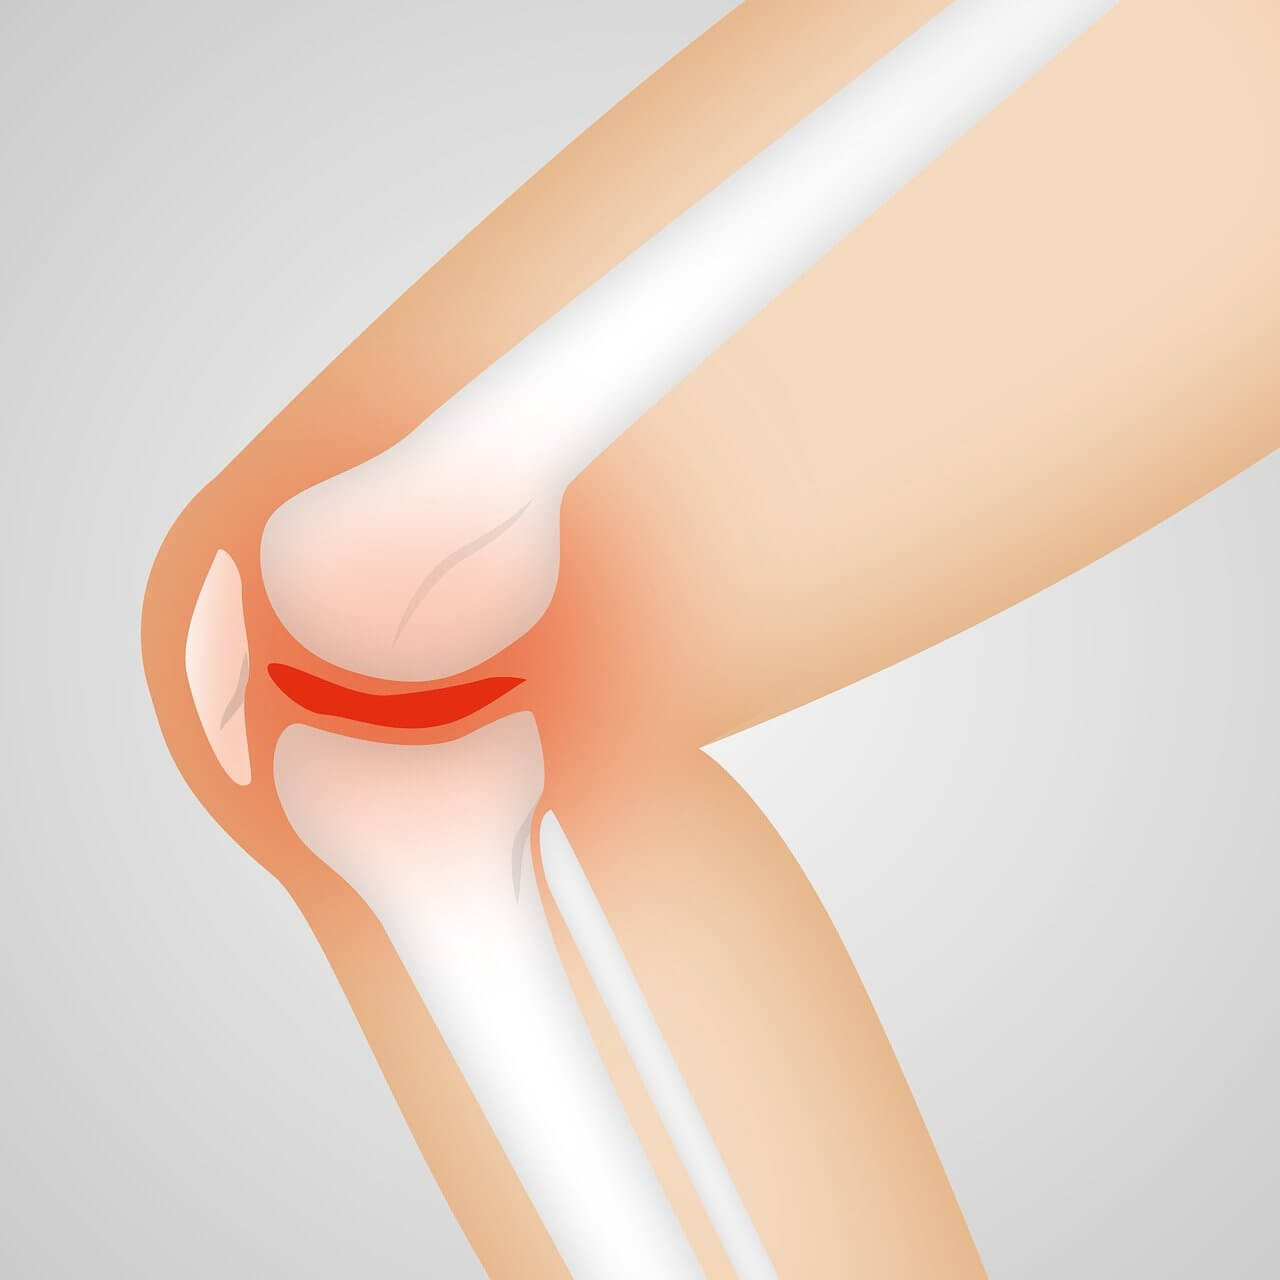

무릎 퇴행성 관절염 생기는 이유

무릎은 매일 쓰는 관절이기 때문에 나이가 들수록 빠르게 닳습니다. 연골이 닳아 없어지면 뼈끼리 마찰되면서 통증, 부종, 뻣뻣함이 생기게 되는데요. 초기에는 별다른 증상이 없다 보니 많은 분들이 방치하다가, 나중엔 걷기도 힘든 상태까지 악화되곤 합니다.

그래서 조기 발견과 치료가 정말 중요해요!